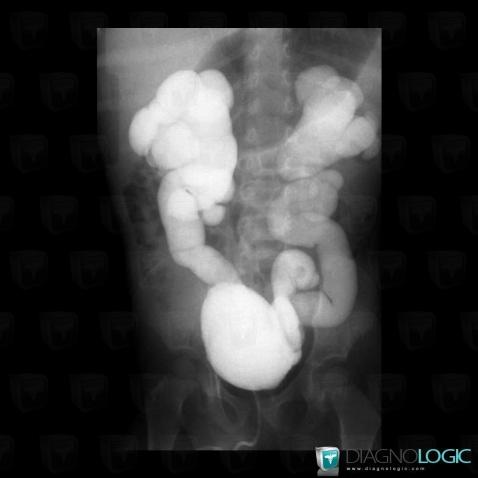

Duplicated collecting system, Ureter, US

Here is the specific information in the key image above:

- Diagnosis Duplicated collecting system, Location(s) Ureter, with gamuts